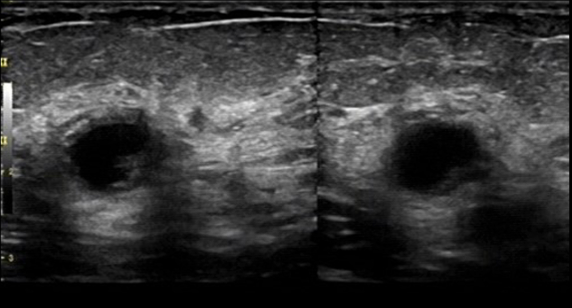

Bệnh nhân: 39 tuổi, có khối u sờ thấy được.

Tình trạng: Xuất hiện các khối giảm âm giới hạn rõ ở cả hai vú.

- HHUS: Phát hiện khối u sờ thấy ở vú trái (BI-RADS 4) và khối vùng sau quầng vú phải (BI-RADS 3).

Hình 5. HHUS: Bên trái: khối sờ thấy được ở vú trái (BI-RADS 4) – Bên phải: khối sau quầng vú ở vú phải (BI-RADS 3).